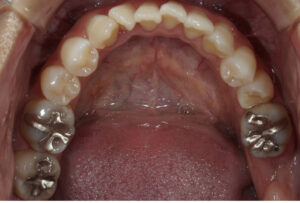

下